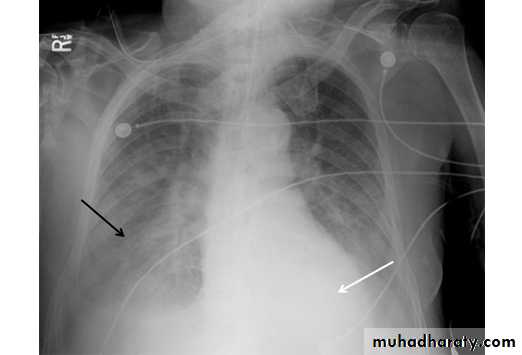

Tension pneumothorax

Hydro pneumothorax

56.tension pneumothorax left sided aspect

57. tension pneumothorax right sided aspect

58.hydropneumothorax